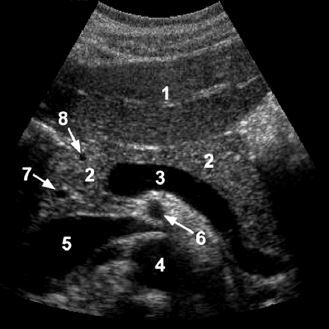

A

1. right thyroid lobe

2. thyroid isthmus

3. carotid

4. IJV

5. trachea shadow

6. strap muscles

7. sternocleidomastoid muscle

8. longus coli muscle

The thyroid is more echogenic than the overlying strap muscles and the sternocleidomastoid muscles.